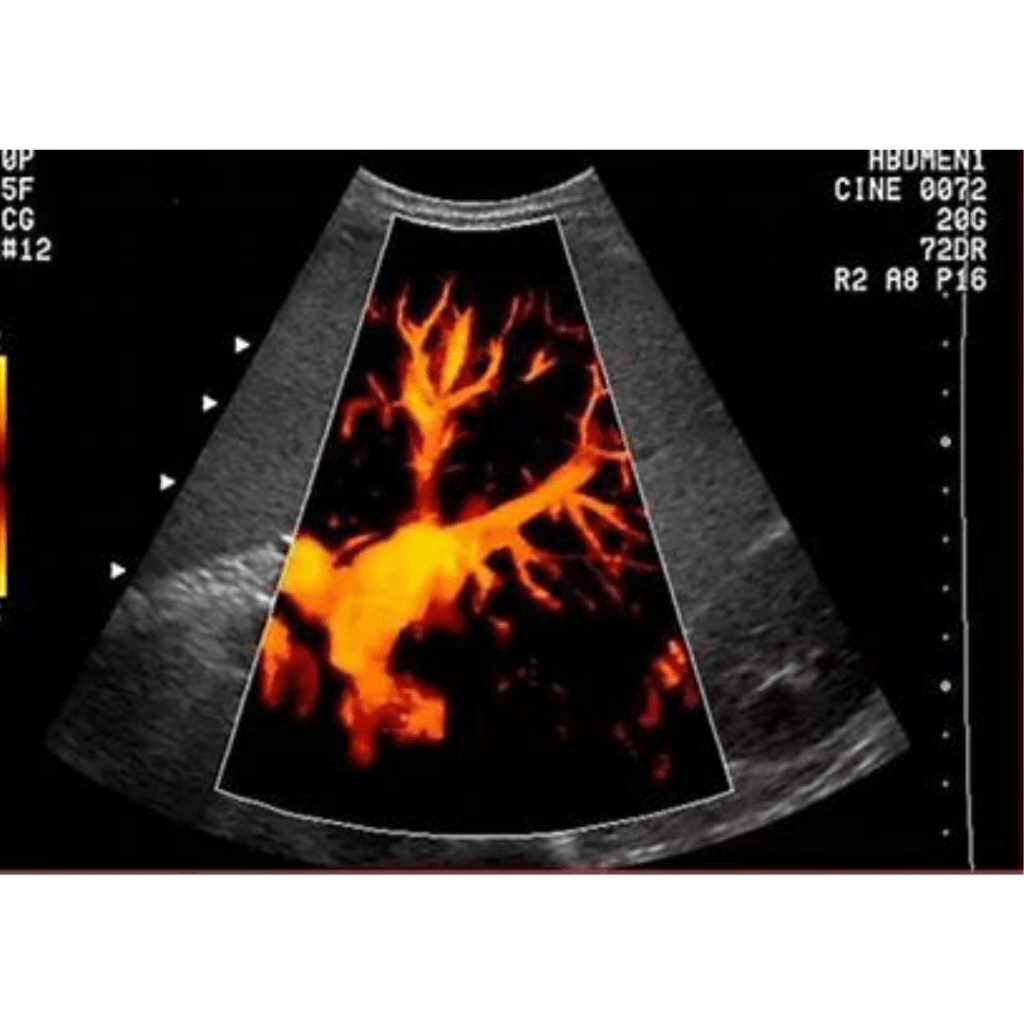

Vascular ultrasound is a non-invasive imaging test that uses high-frequency sound waves to evaluate the body’s circulatory system, specifically the arteries and veins. This procedure helps identify blockages, blood clots, and other vascular conditions.

Diagnosing Vascular Conditions: Vascular ultrasounds are essential for detecting issues such as blood clots, narrowed blood vessels, and other abnormalities in the circulatory system.

Evaluating Blood Flow: The test assesses how blood flows through your arteries and veins, aiding in the diagnosis of conditions like peripheral artery disease and venous insufficiency.

Guiding Treatment Plans: Results from a vascular ultrasound can help healthcare providers determine the most appropriate treatment options, such as angioplasty or monitoring blood vessel health after bypass surgery.